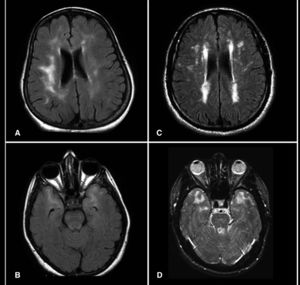

Hyperintensities (bright areas on MRI scans above) are 2.5 times more likely to occur in bipolar disorder